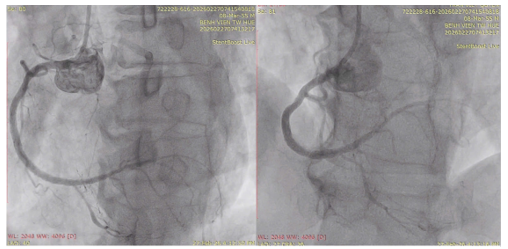

Hình 2. Kết quả chụp động mạch vành: hẹp 50–60% đoạn xa thân chung, hẹp khít 99% động mạch liên thất trước đoạn gần (LAD) (mũi tên hình A và B), hẹp 70–80% động mạch mũ (LCx) và tắc mạn tính động mạch vành phải (RCA) (mũi tên hình D).

Với kết quả trên, bệnh nhân có chỉ định can thiệp cấp cứu LAD, can thiệp trì hoãn RCA.